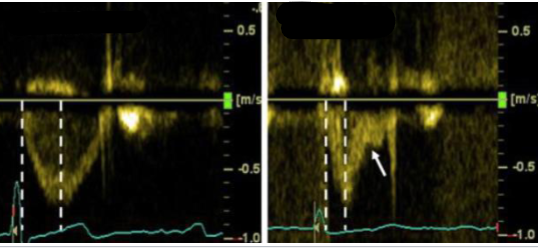

Compare these two tracings of the same valve on different patients. What valve is being measured? Which is normal and which is abnormal? What does the abnormal tracing indicate?

PV PW.

Left is normal with normal acceleration time, peak in the middle of the waveform, and appropriate deceleration time.

Right is abnormal with shortened acceleration time, an early peak, and a mid-systolic notch. These are indications of pulmonary HTN.

Explain why a PV mid-systolic notch may occur in the spectral tracing.

The PV starts closing because the RV pressure and PAP equalize but the RV is still contracting - generates enough pressure to push the leaflets open again.